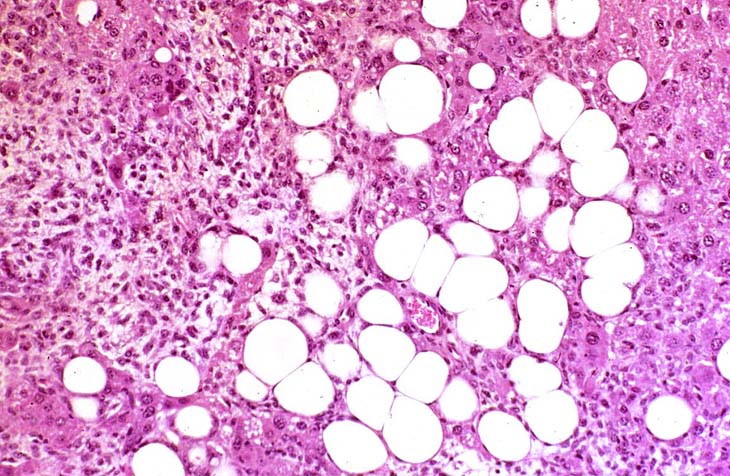

This Ito cell tumor is comprised of a mixture of stellate cells and mature adipocytes.